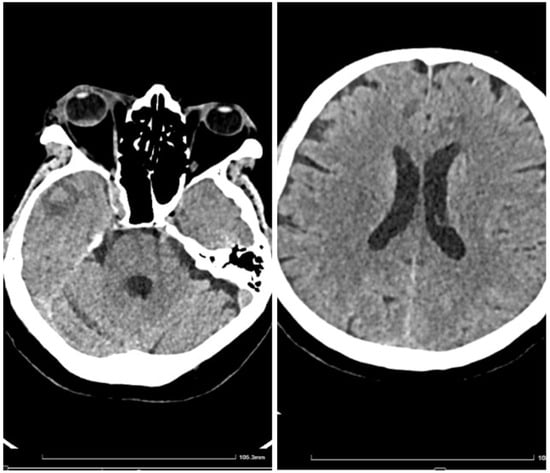

It was suspected that there was a metastatic tumor, and a full-body CT scan was performed (Figure 2). The CT scan discovered multiple abscesses in the lungs and under the skin. A second contrast MRI (Figure 3) scan was conducted which revealed abscesses in all parts of the brain, including the right thalamus and left cerebellar hemisphere, with ring-like contrast-enhancing lesions. However, the lesions were relatively stable compared to the previous MRI.

The full-body CT scan showed multiple nodular cavitating lesions spread throughout the pulmonary area and several subcutaneous abscesses in various locations, with one notable abscess in the distal portion of the anterior serratus muscle and right pre-pectoral subcutaneous fat. Additionally, there were multiple nodules on the peritoneum and perisplenic fat, all measuring between 2 and 3 cm in diameter.

Figure 2. CT with contrast, showing disseminated lesions in the lungs, abdomen, and soft tissues (the green arrows indicate disseminated abscesses, blue arrow indicates drained abscess).